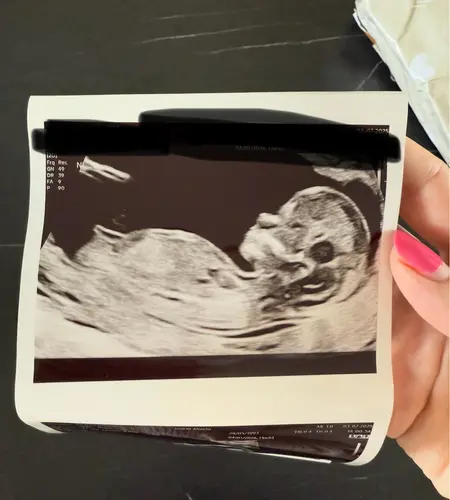

Wat denken jullie aan de hand van de Skull?馃挋馃┓

Jongen 馃┑

Jongen

Ja?? Vond echo zo anders dan bij m'n zoon 馃槄

Een jongen 馃挋